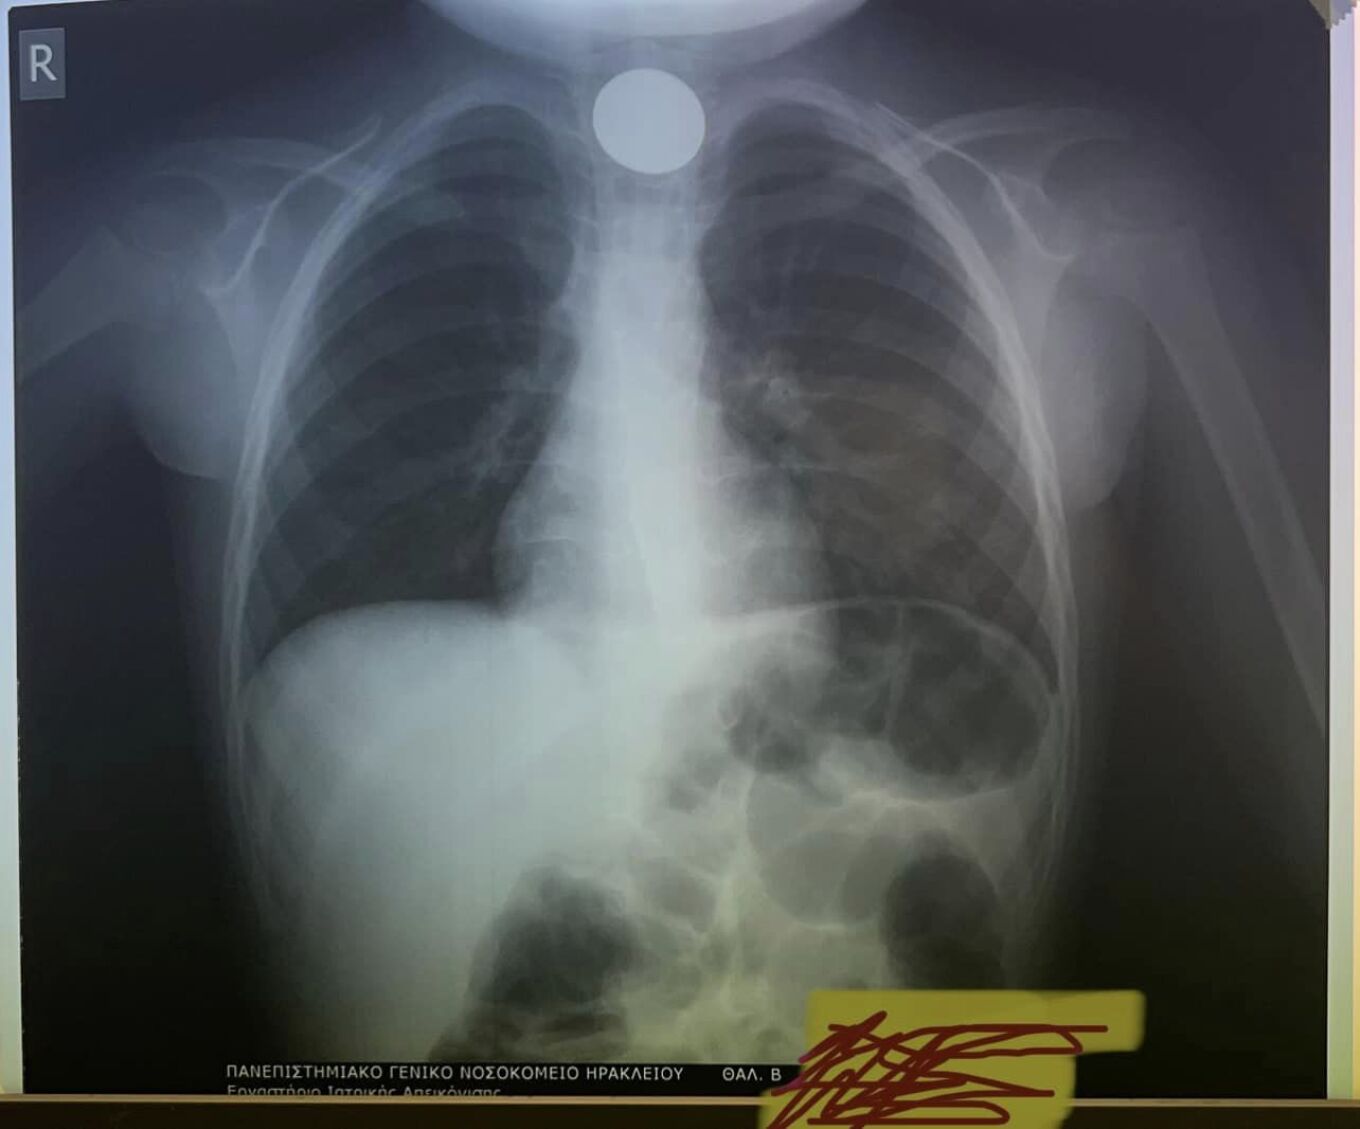

Αγωνία για 4χρονο στην Κρήτη που κατάπιε κέρμα και στάθηκε στον λαιμό του – Δείτε την σοκαριστική ακτινογραφία

Αγωνία επικράτησε στο Ηράκλειο Κρήτης για 4χρονο αγοράκι, καθώς το παιδί κατάπιε κέρμα που μάλιστα του στάθηκε στον λαιμό.

Η πρώτη κίνηση των γιατρών, ήταν να του κάνουν ακτινογραφία, για να δουν το σημείο που είχε σταθεί το νόμισμα.